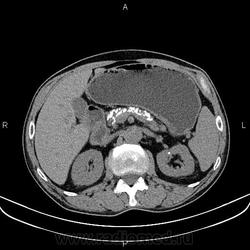

Каменюки в поджелудочной железе?

Добавил КТ. Жаль криволинейной реконструкции на станции нет.

Недавно был такой случай, долго думал и искал... Потом на радиопедии нешел что это хронический панкреатит, да и по поводу обзорки, на обзорной рентгенограмме не стоит все похожие кальцинаты списывать на поджелудочную так как это может быть и аденокарцинома толстой кишки.